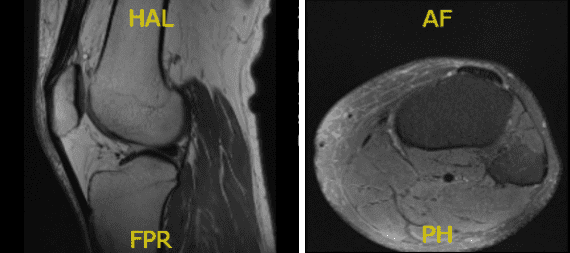

MRI presented and reviewed by the doctor. It showed that the left knee of the patient is intact in medial and lateral meniscus and has no acute osseous injury but has small joint effusion. The central trochlea has a focal chondral fissure and fibrillation in the midportion of the medial femoral condyle.

However, the right knee of the patient, prior partial lateral meniscectomy with diminutive anterior horn with a re-tear in the body of the lateral meniscus. Because of the extrusion of the body the lateral meniscus causes too mild to moderate tricompartmental osteoarthritis with small joint effusion.

The left knee x-ray that completes with patella shows that there are no acute fractures and significant degenerative changes while the right knee has no fractures but have mild osteoarthritic degenerative changes.